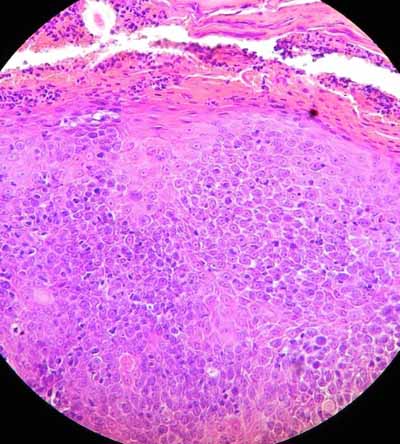

Les calques cutanés réalisés après retrait des croutes révèlent une réaction inflammatoire non spécifique avec surinfection bactérienne. L’analyse histopathologique de deux biopsies de la truffe, réalisée par Frédérique DEGORCE du LAPVSO, montre un épiderme hyperplasique et hyperkératosique recouvert d’un magma crouteux séro-cellulaire, à partir duquel prolifèrent des cordons épithélieux anastomosés et ramifiés, formant une prolifération épithéliale à localisation dermique associée à une stroma-réaction inflammatoire marquée. Les cordons cellulaires montrent un agencement pavimenteux et plan de cellules épithéliales polyédriques unies par des ponts épineux, avec kératinisation individuelle et collective (globes cornés). L’activité mitotique, l’anisocaryose et les atypies cyto-nucléaires sont faibles. Aucune image d’embolisation ni d’effraction vasculaire n’est constatée (photos 4, 5 et 6). L’analyse virale par PCR de prélèvements de truffe est négative.

Photo 5 et 6 : Observation microscopique (x400) d’une biopsie de la truffe.

Noter l’agencement pavimenteux et plan des cellules épithéliales polyédriques.